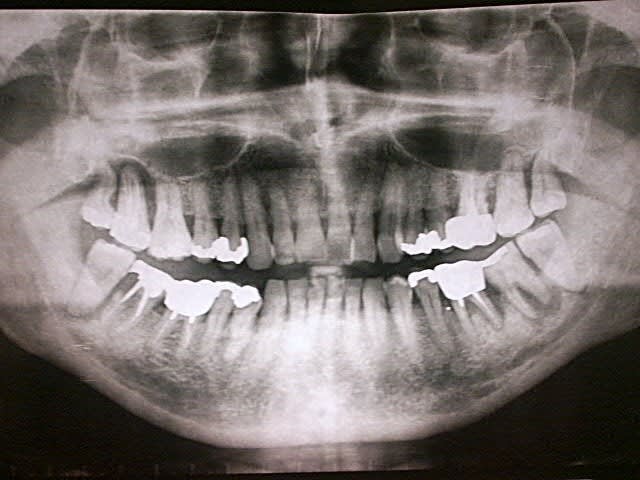

patient, 65 ans, ami proche de la famille, pére d'un très bon ami d'enfance.

douleurs récurrentes au maxillaire droit à la mastication.

sensations de dents + ou - mobiles au max D et mand G.

Habitudes: visite annuelle chez son CD. a effectué les soins et prothèses conseillés. Pas de gros travaux entrepris depuis 20 ans. utilise un hydropulseur en plus du brossage (mais ne sait surement pas que son efficacité sur la PD est nulle).

Dernière visite chez son CD: 3 mois... pour la même raison. RAS tout va bien (???) + un ATB et roule ma poule... (???).

n'a plus trop confiance dans son CD...

motivation: ok. prêt à faire des kms pour venir me voir. prêt à faire de gros rdv (2H).

Je l'ai envoyé faire une pano en attendant de le voir en consultation. Bigre!!!!

premières impressions?

Manifestement alvéolyse horizontale généralisée, 25% de perte d'attache à 65 ans : je penche pour une parodontite chronique de l'adulte.

Je soupçonne aussi un trauma occlusal.

Je ne doute pas que tes talents en endo permettront de sauver ce qui l'est (bonne chance pour 36).

Mais 47 est HS.

Ouais, l'usure occlusale est quand même flagrante.

Implant sur 47 et je crois que je me séparerais des sagesses, z'ont pas l'air catholiques.

moi, c'est la 17 qui me chagrine le plus.

la racine distale de 47 est morte. Première impression: la virer, garder la racine M, petit bridge pro en résine renforcée en attente de stabilisation du pb paro et assurer calage de 48. Voir par la suite pour implant ou bridge.

ce cas présenté par tonio est un classique .....parodontite de l'adulte surement plus facteur occlusal ( cette patiente est en béance incisvo canine surement )

pour moi 17 18 28 perdues

48 pas très interessante si 18 pas conservée en plus elle est extrusée.....faire de l'odf alourdira je pense beaucoup pour un résultat pas forcemment supérieur tout en tenant compte de l'age